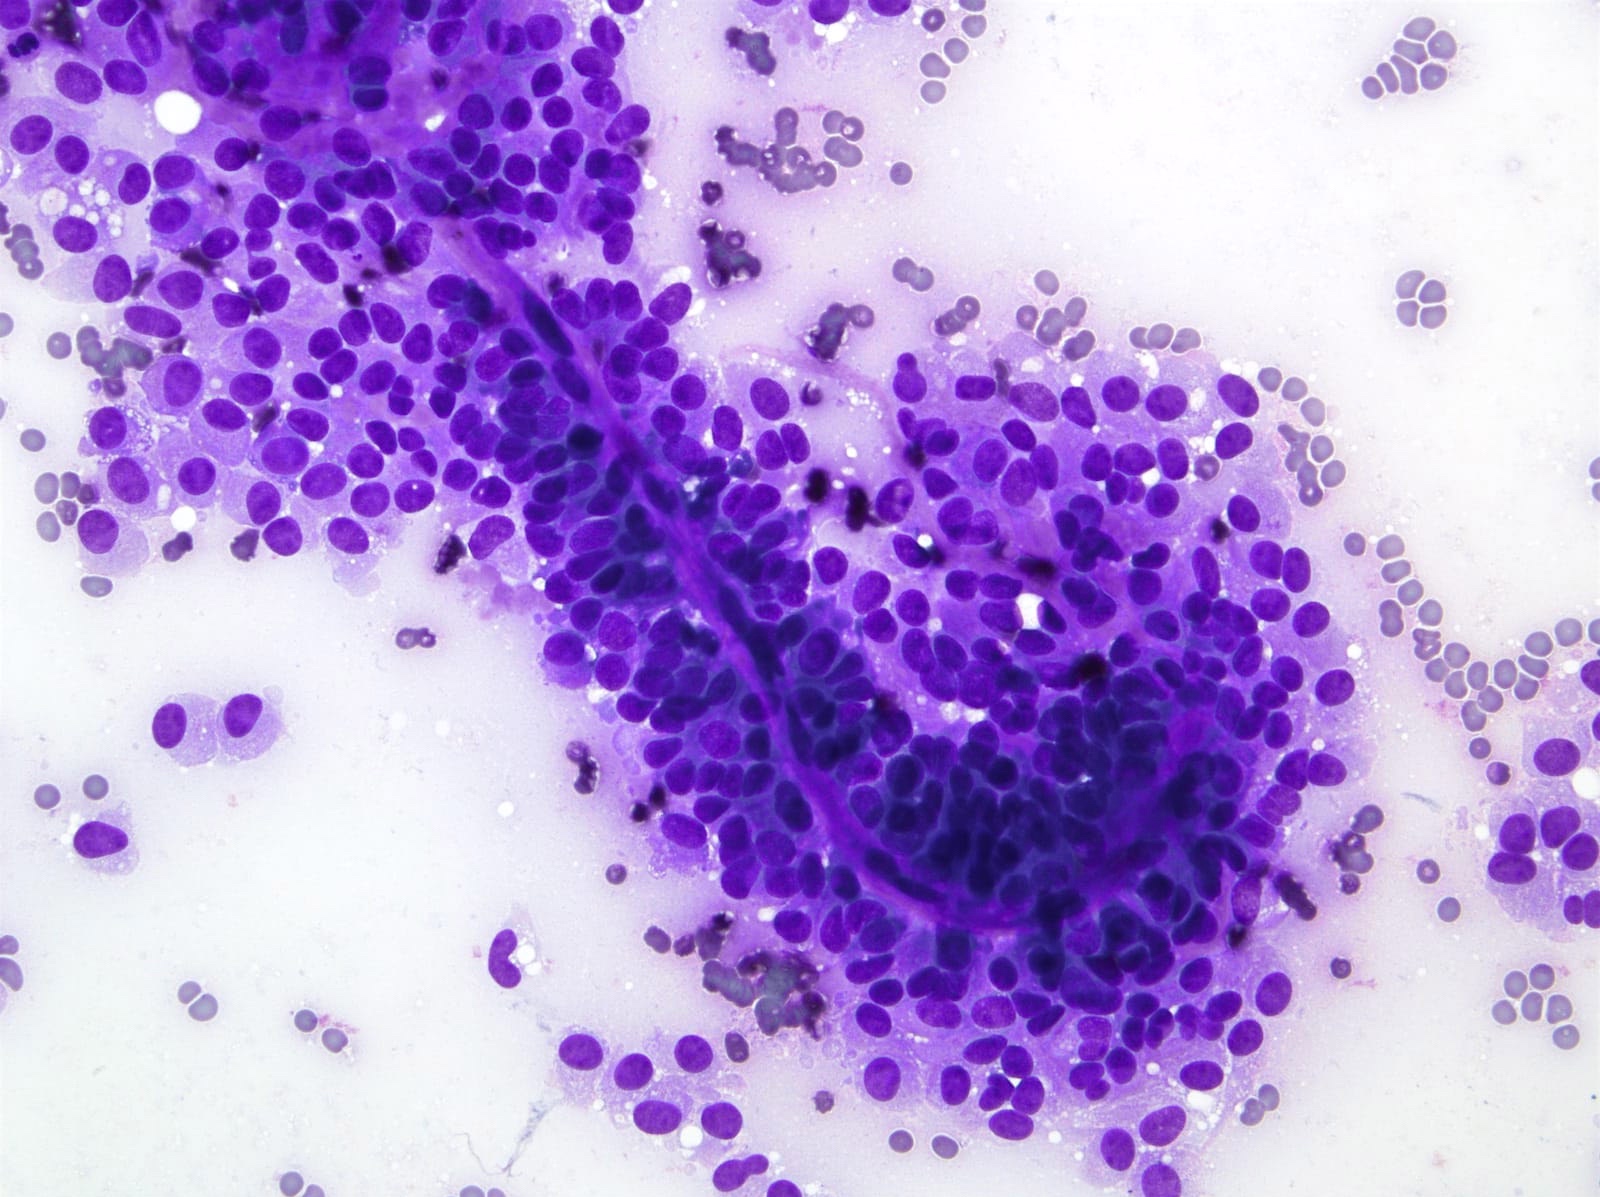

Cytology description

- Cellular smears with delicate papillary fronds

- Tumor cells are usually bland and uniform with a moderate amount of cytoplasm, which usually contains variable sized clear perinuclear vacuoles or cytoplasmic eosinophilic hyaline globules

- Nuclei are round to oval with grooves and finely granular chromatin (J Cytol 2010;27:118, Arch Pathol Lab Med 2017;141:990)

- Cercariform cells, cytoplasmic vacuolation, reniform nuclei, hyaline globules and degenerative features, such as cholesterol crystals, calcifications, foam cells or giant cells, are more commonly seen in solid pseudopapillary neoplasms, compared with acinar cell carcinomas / neuroendocrine tumors (Cancer Cytopathol 2013;121:298)

Cytology images